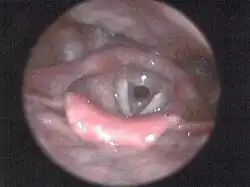

Badania endoskopowe

Badanie endoskopowe dróg oddechowych (bronchoskopia wykonywana metodą sztywnej tracheobronchoskopii, w zestawie do mikrolaryngoskopii lub fiberoskopami z optyką Hopkinsa) zwykle pozwala na dokładną ocenę lokalizacji i długości zwężenia, także niżej położonego, ocenę ruchomości nalewek, stanu błony śluzowej. Możliwe jest także pobranie wymazu lub biopsji i wykonanie zabiegu poszerzania. Ocena długości zwężenia i stanu dróg oddechowych poniżej niego może jednak okazać się niemożliwa przy zwężeniach znacznego stopnia, nie przepuszczających bronchoskopu. Wykrycie, ocena oraz biopsja cienkoigłowa zmian śródściennych tchawicy oraz zmian w strukturach do niej przylegających możliwa jest poprzez bronchofiberoskopię z ultrasonografią wewnątrzoskrzelową przy użyciu specjalnego bronchofiberoskopu wyposażonego na stałe w głowicę konweksową USG (CP-EBUS)[102][103][104][105][106][107][5][7][12].